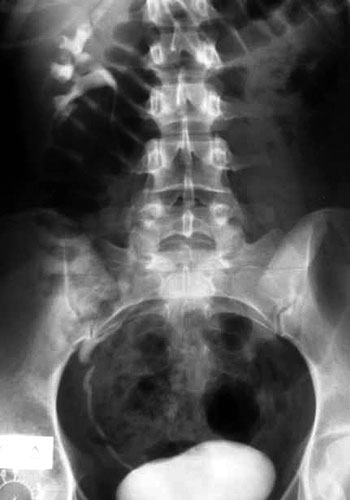

Εικόνα 3. Απλασία ΑΡ νεφρού (ασθενής 5).

Στην τυπική μορφή οι βλάβες αφορούν μόνο το γεννητικό σωλήνα. Στην άτυπη μορφή, σε ποσοστό 15-40%, συνυπάρχουν διαταραχές της διάπλασης του ουροποιητικού συστήματος, όπως ετερόπλευρη νεφρική αγενεσία, έκτοπος, υποπλαστικός ή πεταλοειδής νεφρός και δυσπλαστικές βλάβες στο πυελοκαλυκικό σύστημα ή στους ουρητήρες.(14) Στο 10-15% των ασθενών με την άτυπη μορφή του συνδρόμου παρατηρούνται σκελετικές ανωμαλίες που αφορούν κυρίως τη σπονδυλική στήλη, τις πλευρές, το προσωπικό κρανίο ή τα άκρα, όπως σκολίωση, στροφοσκολίωση, σφηνοειδής παραμόρφωση των σπονδύλων, συνένωση των σπονδύλων, δισχιδής ράχη, ιεροποίηση του 5ου οσφυϊκού σπονδύλου, βραχέα μεσοφαλαγγικά οστά, υποπλασία του σκαφοειδούς και υποπλασία του τραπεζοειδούς οστού.(5,14) Σε μικρότερα ποσοστά αναφέρονται κώφωση, βουβωνοκήλη ή μηροκήλη.(14,15) Η ασθενής 5 πάσχει από την άτυπη μορφή του συνδρόμου και οι διαταραχές από τον σκελετό και τους νεφρούς (εικόνα 3) είναι αναμενόμενες. Από τις ασθενείς με την τυπική μορφή, μόνο η ασθενής 2 δεν είχε διαταραχές στη διάπλαση από τους νεφρούς ή τον σκελετό. Oι ασθενείς 3, 4 (εικόνα 4) και 6, παρόλο που έπασχαν από την τυπική μορφή του συνδρόμου, είχαν δυσπλαστικές βλάβες τόσο από τους νεφρούς όσο και από τον σκελετό.